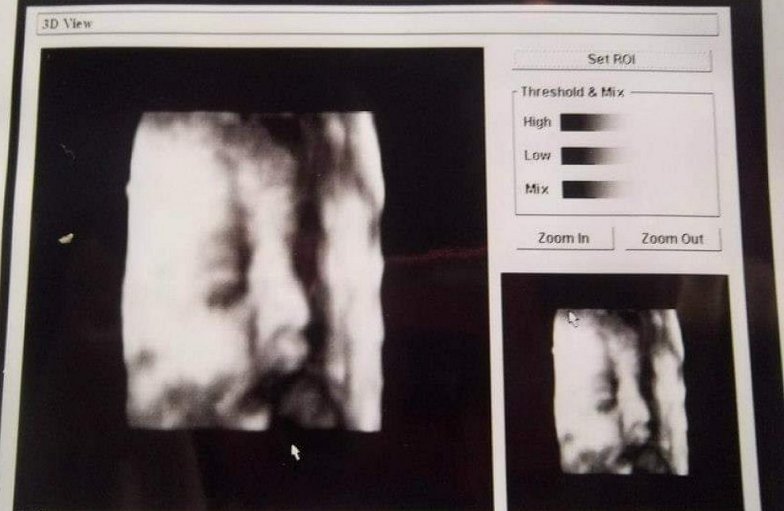

Por su parte, "la obtención de la imagen en tres dimensiones (3D) se realizó siempre a solicitud de la paciente, atendiendo el legítimo interés de los padres de conocer el rostro de su hijo o hija de manera anticipada, (pero) no teniendo bajo ningún punto de vista un fin diagnóstico", dijo Andaur.

"En relación a lo ocurrido, quisiera aclarar que, de manera involuntaria al momento de imprimir la imagen en 3D, esta correspondía a una foto configurada previamente por el fabricante del equipo a modo de demostración", explicó.

De este modo, el facultativo indicó que "dicha foto no corresponde a la captura 3D de otro paciente, como se ha señalado en algunos medios de comunicación y redes sociales".

Imagen foto_00000016

La imagen que repartía Oliva no era de ninguna de sus pacientes, sino una demostración "configurada previamente por el fabricante del equipo".